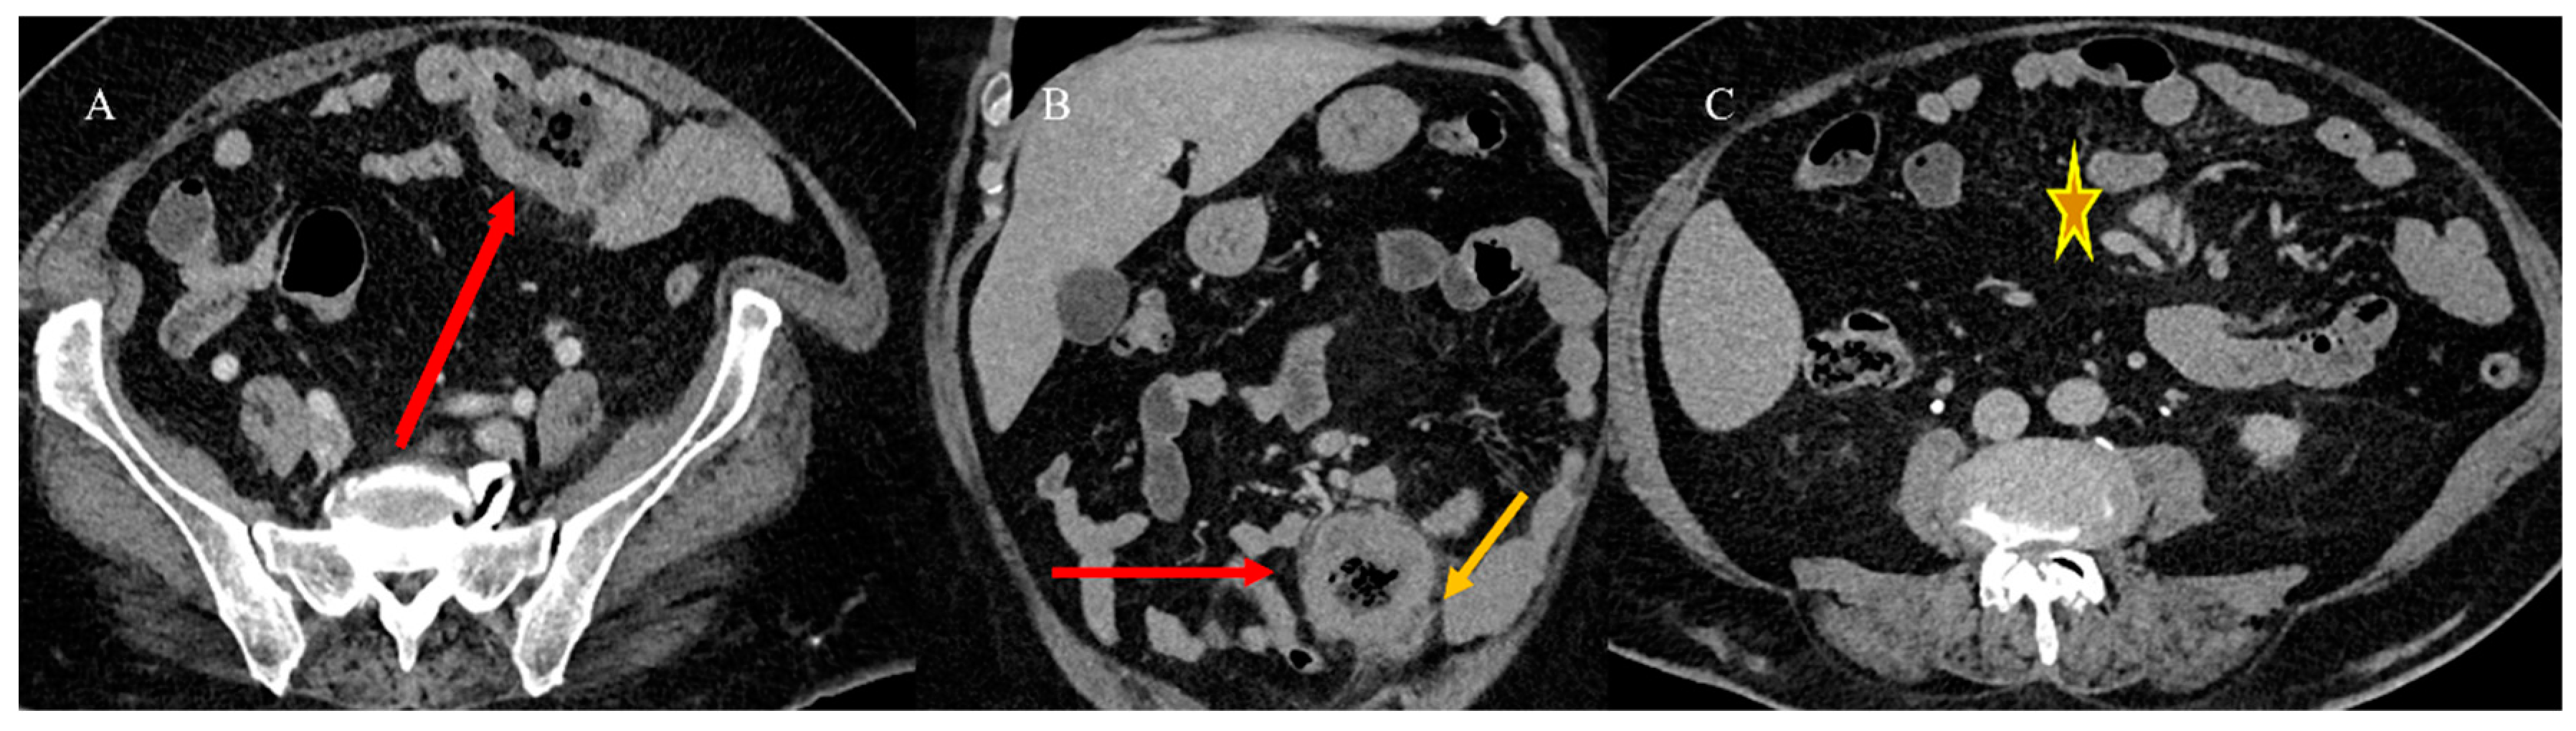

2.3. Small Bowel Tumor Presentation in Emergencies with Intestinal Intussusception

2.4. Small Bowel Tumors Causing Small Bowel Occlusion

2.5. Small Bowel Tumors Presenting with Bleeding, Ischemia, and Perforation